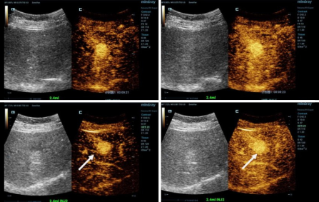

![Diagn├│sticos m├ís precisos con HiFR CEUS]() Diagn├│sticos m├ís precisos con HiFR CEUSLa ecograf├şa potenciada con contraste (CEUS) es un campo muy din├ímico y en los ├║ltimos a?os las innovaciones tecnol├│gicas han aumentado a├║n m├ís la calidad de la imagen. Una de estas innovaciones es la ecograf├şa potenciada con contraste de alto frame-rate(HiFR CEUS), que puede generar hasta diez veces m├ís im├ígenes que el ultrasonido convencional, sin demorar m├ís tiempo.Ecograf├şa | Im├ígenes medicina general 2023-04-28

Diagn├│sticos m├ís precisos con HiFR CEUSLa ecograf├şa potenciada con contraste (CEUS) es un campo muy din├ímico y en los ├║ltimos a?os las innovaciones tecnol├│gicas han aumentado a├║n m├ís la calidad de la imagen. Una de estas innovaciones es la ecograf├şa potenciada con contraste de alto frame-rate(HiFR CEUS), que puede generar hasta diez veces m├ís im├ígenes que el ultrasonido convencional, sin demorar m├ís tiempo.Ecograf├şa | Im├ígenes medicina general 2023-04-28 -